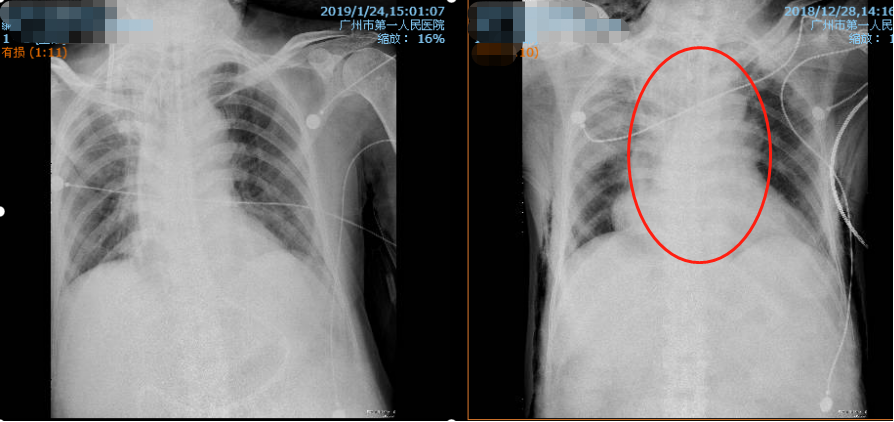

左图为出院后的状况,右图为入院时的状况 图/张华

在医护人员的共同努力下,病情终于得到控制、好转。患者呼吸困难缓解,顺利脱离呼吸机,纵膈引流管引流液明显减少,痰量逐渐减少,痰色由黄色转白色,出院前在无吸氧下能坐轮椅在病区活动。经一系列复查提示患者纵膈脓肿明显吸收,皮下气肿消失,已安排出院。后续只需遵医嘱恢复治疗即可。

在收治入院的当天,医生们马上给李伯做了颈部、胸部、腹部CT,CT见纵隔大量积脓引流不畅,而且合并呼吸衰竭、心率>120次/分,血压不稳多脏器功能障碍等严重脓毒血症表现,因此诊断为“食管-纵膈、气管瘘、呼吸衰竭。”呼吸与危重症医学科赵子文主任团队立即请了胸外科等专家来进行会诊。食管-纵膈瘘死亡率高,会诊意见都认为患者很难挺过来。